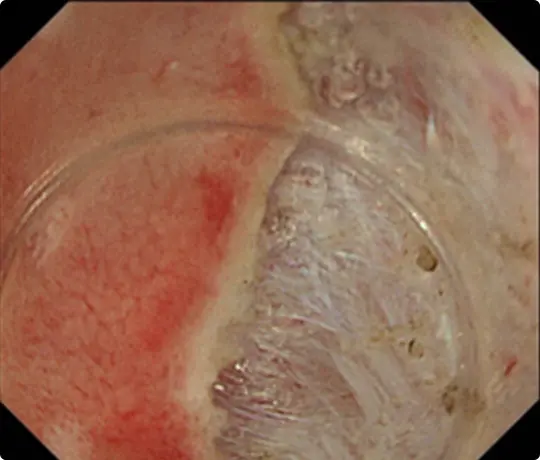

約4cmの高度な線維化を伴う早期大腸がんに対するESDを提示します。当科で考案したUnderwater ESD(生理食塩水の中で行うESD)が有効でした。

重症の潰瘍性大腸炎の既往があり、高度な線維化により難易度が高いと予想されました。

粘膜の下に液体を注入して病変を浮かせます。

病変の外側の粘膜を電気メスで切開したところです。

粘膜の下の組織(粘膜下層)を電気メスで剥がそうとしていますが、高度な線維化で筋層との境界がよく分かりません。このままでは筋層を傷つけて穴をあけてしまうリスクがあります。

当科で考案したUnderwater ESD(生理食塩水の中で行うESD)を行うことで光の反射がなくなり、拡大効果もあるため、鮮明な視野が得られ粘膜下層と筋層の境界が分かりやすくなります。筋層を傷つけないように、精密に剥離することが可能になります。

穿孔(壁に穴があくこと)などの問題なく、病変を切除しました。切除後は潰瘍が出来ますが、1~2ヵ月で治ります。

切除した検体をピンで伸ばしています。ホルマリンで固定後、病理診断を行います。病理診断で腫瘍は完全に切除されており、治癒と判定されました。